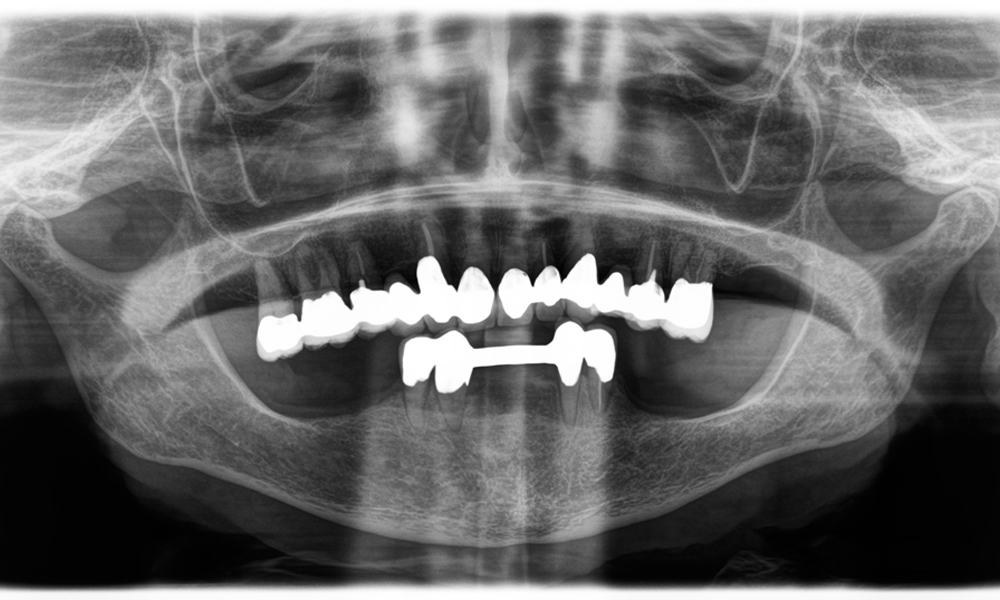

A second case highlighting the clinical capabilities of the Power Edition involved the replacement of a damaged zirconia crown in a 63-year-old patient. The patient presented with a chipped veneer on her 20-year-old zirconia crown on tooth 6. Despite the posterior location, the patient found the defect bothersome and requested a new restoration.

The Power Edition enabled precise sectioning, with the increased torque and enhanced cooling contributing to the controlled removal of the crown without significant material loss. The chucking system and enhanced torque proved to be essential in this process.